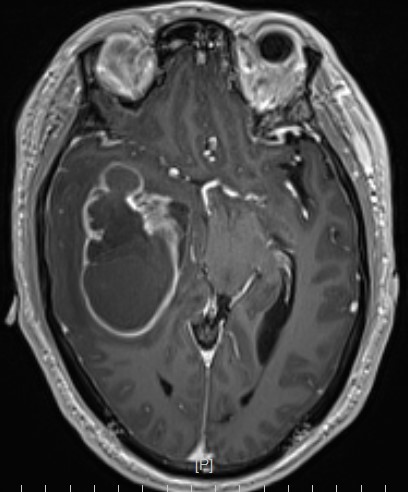

患者,男性,59岁,头痛伴四肢无力一周入院

头部MR提示:右颞叶,岛叶及基底节区巨大占位,胶质母细胞瘤可能性大